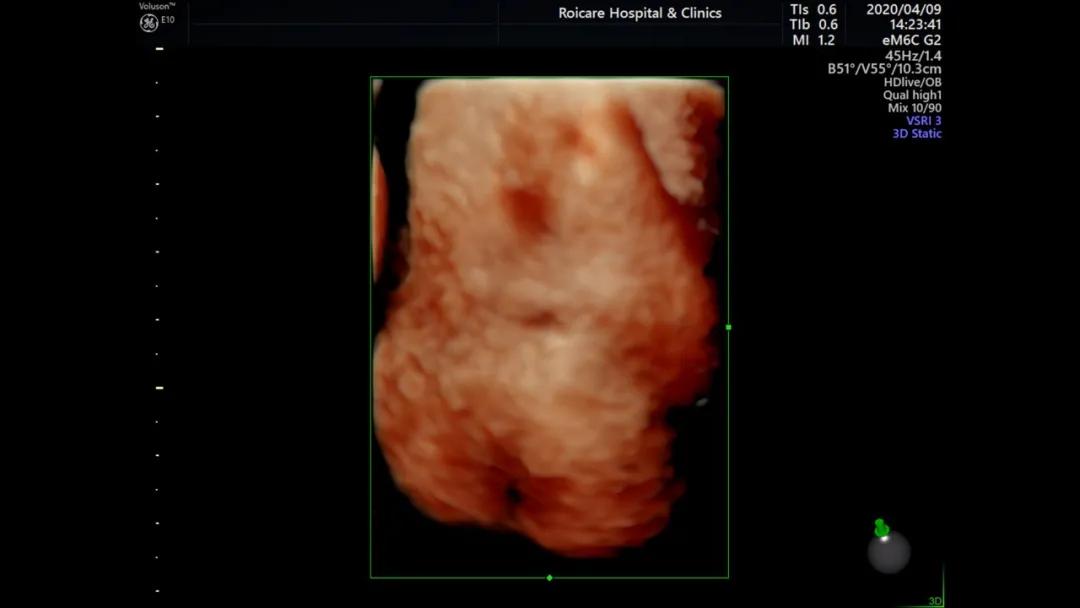

脊髓圆锥低位

脊柱裂

对于脊髓圆锥低位但影像学检查没有发现明确原因的胎儿应建议复查,观察脊髓圆锥是否上升,不可盲目引产。部分闭合性脊柱裂可能无任何临床症状。随着神经显微外科的发展,闭合性脊柱裂已取得较好临床疗效。